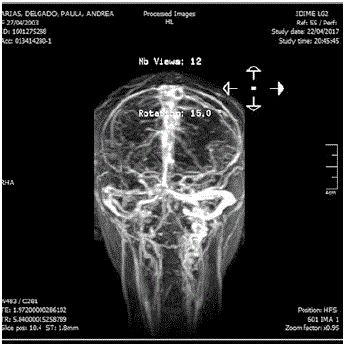

Al ingreso manifestaba intenso dolor cervical, afasia motora, desviación de la mirada a la derecha, sialorrea, hemiparesia izquierda, Babinsky izquierdo, reflejo rotuliano izquierdo exaltado y no mostraba alteración en la sensibilidad ni signos meníngeos. Su talla es de 173 cm (por encima del percentil 95), delgada, extremidades largas y con aracnodactilia. El TAC cerebral simple evidenció trombosis de varios senos venosos (figura 1); el estudio se complementó con Angio TAC cerebral (figura 2), resonancia magnética cerebral (figura 3) y Angio resonancia cerebral contrastada (figura 4), que confirman la trombosis de los senos venosos. Después de diagnosticar accidente isquémico se trasladó a la unidad de cuidados intensivo (UCI) y se anticoagula con enoxaparina. No necesitó soporte inotrópico ni ventilatorio y posteriormente se llevó a pisos. El ecocardiograma y el doppler carotideo fueron normales. No se encontró dislipidemia y el estudio de enfermedad autoinmune fue negativo. Los exámenes para trombofilia, tomados en etapa aguda, solo mostraron una proteína S ligeramente disminuida (57 %, VN de 59 a 118 %), al igual que la antitrombina m (58,8 %, VN 83-128 %). Se ampliaron estudios con ácido fólico y vitamina B12 en sangre, al igual que los ácidos orgánicos en orina por cromatografía; todos estaban normales. Los aminoácidos en sangre mostraron elevación de la metionina (63 µmol/L, VN de 10 a 45 µmol/L) y la homocisteina (3 µmol/L, VN de 0 a 1 µmol/L) con cistationina baja (0, VN de 0 a 3 µmol/L). El estudio de homocisteina en sangre fue de 214 µmol/L (VN en mujer de 5,08 A 15,39 µmol/L), lo que confirmó el diagnóstico de homocistinuria por deficiencia de CBS.